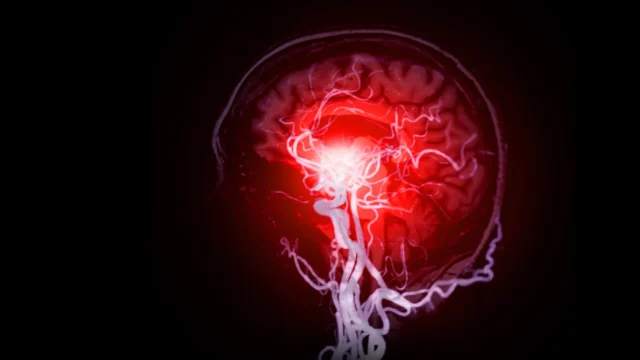

A demência vascular – comprometimento cognitivo causado por doenças de pequenos vasos sanguíneos no cérebro – é um problema generalizado, mas não foi estudado tão minuciosamente como a doença de Alzheimer, que deposita placas anormais e emaranhados de proteínas no tecido nervoso.

Bearer identificou 10 processos de doenças diferentes que levam a lesões cerebrais vasculares, normalmente causando deficiências de oxigênio ou nutrientes, vazamento de soro e inflamação ou redução da eliminação de resíduos. Isso pode causar pequenos derrames, danificando os neurônios. Ela lista técnicas experimentais novas e existentes, incluindo manchas especiais e novos microscópios, para detectá-los.

No artigo, Bill usou microscópios especializados para estudar de perto o tecido de um repositório cerebral doado pelas famílias dos novos mexicanos que morreram de demência, usando manchas para destacar vasos sanguíneos danificados. Surpreendentemente, muitos pacientes diagnosticados com doença de Alzheimer também apresentam doenças nos pequenos vasos sanguíneos do cérebro.